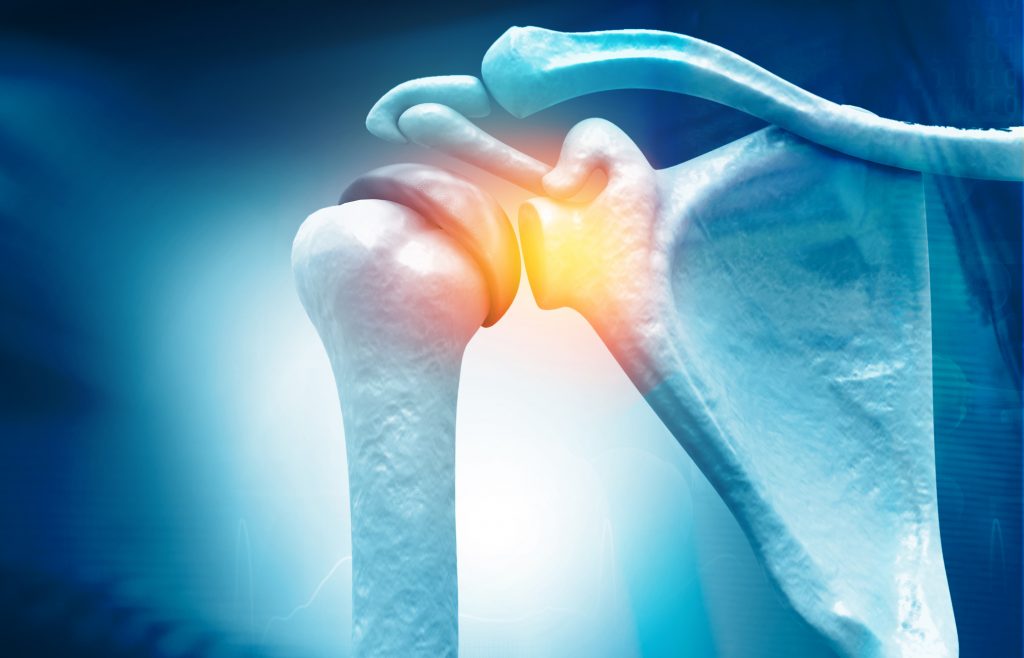

Una delle principali diagnosi per dolore di spalla, e quella che affrontiamo in questo articolo, è quella di impingement o conflitto sub-acromiale.

Il dolore originato da questa condizione sarebbe dato da una riduzione dello spazio sub-acromiale che provocherebbe uno schiacciamento del tendini del sovraspinato o del capo lungo del bicipite.

Il dolore può essere quindi dato da una infiammazione con ispessimento e irritazione della borsa o dei tendini della cuffia dei rotatori, nella zona inferiore dell’acromion.

Per questo la condizione prende il nome di sindrome da conflitto sub-acromiale